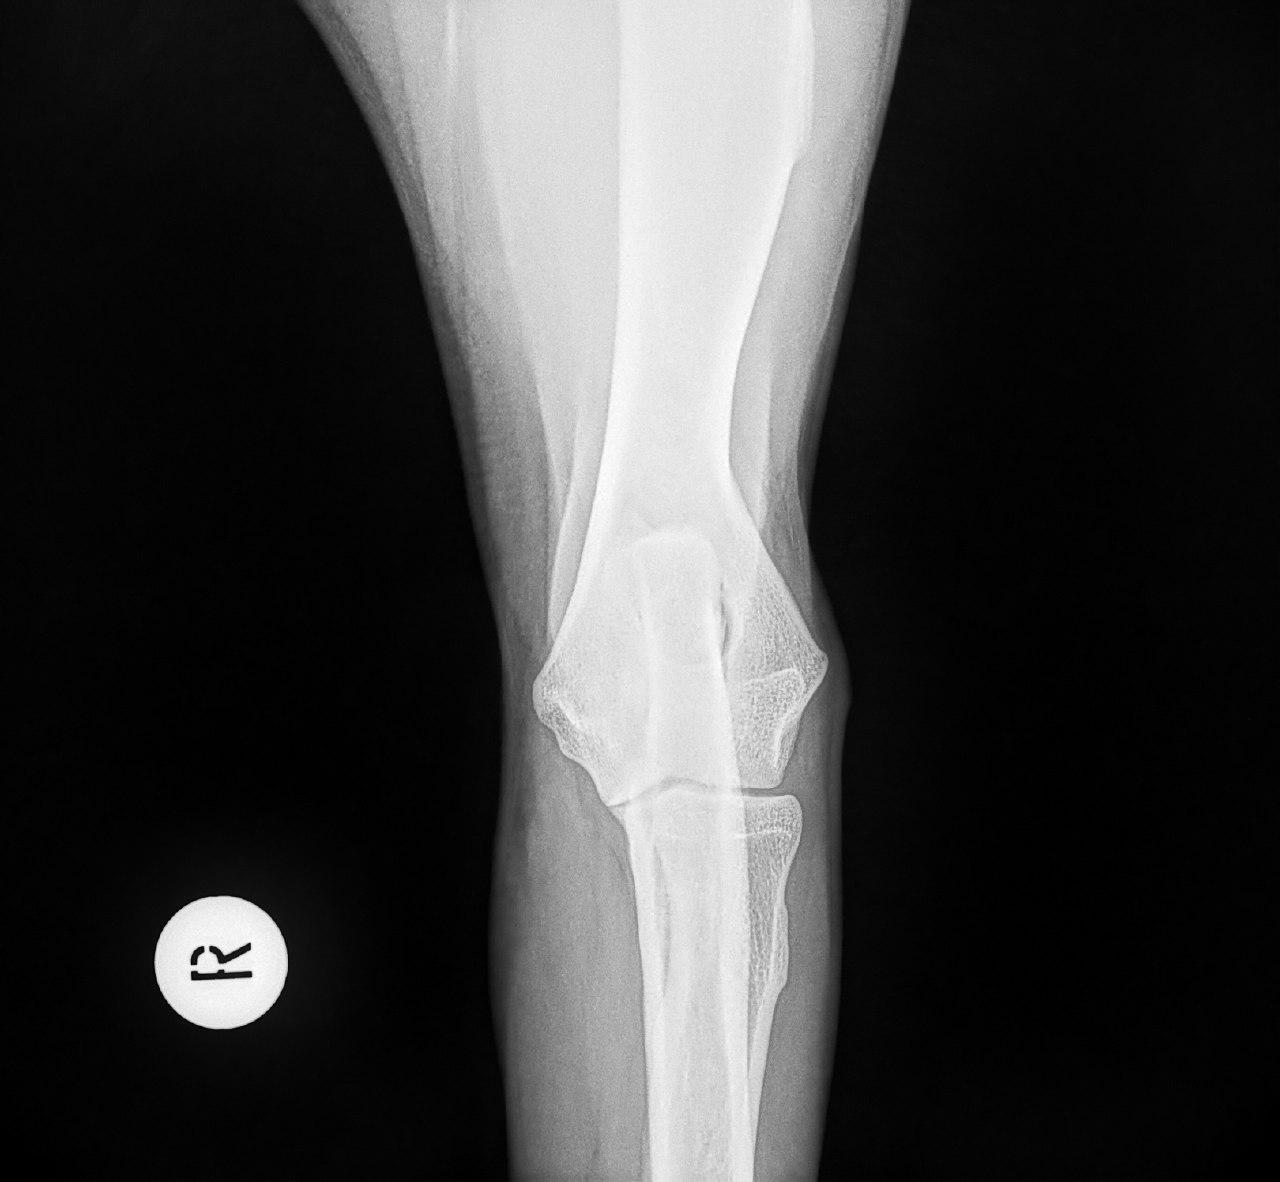

Mit der HD ist das so ne Sache..... die Vererbung spielt eine sehr große Rolle, ja. Aber bei unserer Peggy Zb ist es so, dass mehrere Generationen nachweislich HD und ED frei sind und auch frei von Spondylosen. Als einziger Hund überhaupt in der gesamten Zucht hat unsere Dame alles mitgenommen, was zu kriegen war;(: sie hat nicht nur schwere HD, weil ihre Hüfte viel zu locker ist, sondern dadurch bedingt am rechten Knie bereits schwere Arthrose und hinten links eine Sehenschwäche (durch Überlastung), weshalb sie dort durchtrittig ist. Und als würde das alles nicht schon vollkommen reichen, wurden aktuell auch noch mehrere heftige Spondylosen diagnostiziert;(. An einer Stelle ist sogar schon etwas abgebrochen8|.

Trotzdem hat er mittlere HD und ich fühle mich auch irgendwie total schuldig.